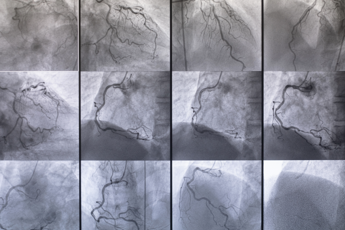

(Adnkronos) – Dietro quasi ogni patologia cronica si trova o si affianca una malattia vascolare. Facili da prevenire, gravi fino all’amputazione o alla perdita della vita se trascurate, le malattie vascolari – secondo gli esperti – colpiranno un quarto della popolazione italiana. Interessano arterie, vene e linfatici e sono responsabili del 22% delle morti in Italia e fanno perdere 10mila arti all’anno. "Bisogna affrontarle con la stessa determinazione di infarti, ictus e tumori – spiega il presidente della Società italiana di chirurgia vascolare e endovascolare (Sicve) Gaetano Lanza – e richiedono un approccio sistemico di prevenzione e governance". Da qui la nascita della Consulta per le Malattie Vascolari che unisce le grandi Società scientifiche e gode del patrocinio di Agenas e Istituto superiore di sanità. L'annuncio questa mattina in apertura di Welfair 2024, la Fiera del fare sanità, dal 5 al 7 novembre alla Fiera Roma. "Ischemie degli arti, aneurismi, ostruzioni carotidee, aterosclerosi, flebo e linfopatie e tumori vascolari sono tra le più importanti cause di mortalità e invalidità nel nostro Paese – spiega Lanza – E sono responsabili del 22% delle morti, subito dopo infarto miocardico (28%) e ictus cerebrale (25%). Oltretutto, le malattie vascolari risultano in costante aumento per l'incremento nella popolazione dell'età media e di diversi fattori di rischio quali ipertensione arteriosa, diabete mellito, dislipidemie, obesità, fumo, inquinamento, comportamenti e stili di vita non corretti, alimentazione errata e inoltre per predisposizioni genetiche". "Una peculiarità della malattia arteriosa degli arti inferiori, per esempio, è di rappresentare un importante fattore di rischio per patologie arteriose in altri distretti corporei: i pazienti affetti da arteriopatia periferica hanno un rischio molto elevato di presentare patologia coronarica o carotidea, con un corrispondente aumento del rischio di infarti ed ictus" sottolinea Angelo Santoliquido presidente del Collegio italiano di flebologia (Cif). "Accanto a queste ci sono poi le flebopatie croniche e acute, alcune delle quali responsabili di Embolia Polmonare a rischio di morte improvvisa" aggiunge Roberto Di Mitri, presidente della Società italiana di flebologia. Sono, inoltre, sempre più frequenti in una popolazione che invecchia, fragile e polipatologica: un bacino di "oltre 4 milioni di persone che vivono sole, 800.000 persone in cure palliative, e almeno 650.000 con disabilità – precisa Claudio Novali, primario emerito di Chirurgia Vascolare Ospedale di Cuneo e presidente Associazione pazienti malattie vascolari titoccotoccati Aps – È in questo bacino che la malattia aterosclerotica agli arti inferiori (Aocp) – che colpisce oltre il 20% dei pazienti con più di 70 anni – può sviluppare, quando non correttamente curata l’ischemia critica agli arti inferiori, responsabile nel 50 % di questi pazienti delle amputazioni: oltre 11mila ogni anno in Italia. Fra l’altro, un paziente amputato ha un rischio maggiore di incorrere a complicanze cardiache, cerebrali e di mortalità. I dati in nostro possesso ci dicono che oltre il 50% dei pazienti amputati non hanno avuto un percorso di presa in carico corretta e tempisticamente efficiente". È per far fronte a questo scenario quanto mai complesso e urgente che nasce la Consulta delle Società scientifiche e Associazioni pazienti per le malattie vascolari. La Consulta unisce alcune tra le più importanti associazioni scientifiche del settore: la Società italiana di chirurgia vascolare endovascolare (Sicve), l’Associazione flebologica italiana (Afi); il Collegio italiano di flebologia (Cif); la Società italiana di flebologia (Sif); la Società di flebolinfologia (Sifl); la Società per lo studio delle anomalie vascolari (Sisav); l’Associazione pazienti prevenzione malattie vascolari (Ttt). "In sintesi, la Consulta – spiega Lanza – nasce per portare le malattie vascolari al centro dell’attenzione e della pianificazione sanitaria. Parliamo alle Istituzioni e ai decisori sanitarie parliamo ai cittadini". "Abbiamo bisogno di programmi di educazione, prevenzione, diagnosi, cura e presa in carico dei pazienti per ridurre un impatto sociale ed economico che, solo per la Malattia venosa cronica (Mcv) a titolo d’esempio, interessa il 40% della popolazione generale e incide per il 2% dell’intera spesa sanitaria" interviene Maurizio Ronconi, direttore S.C. Chirurgia generale ASST Spedali Civili di Brescia e Presidente Associazione Flebologica Italiana. “Nel campo estremamente delicato delle anomalie vascolari – malattie rare che colpiscono il 4-10% della popolazione, congenite e particolarmente invalidanti nell’età fragile dell’adolescenza – l’Italia oggi ha accumulato una grande competenza chirurgica – evidenzia Francesco Stillo, ex presidente Sisav – Negli anni ‘90, l’80 % dei pazienti in Francia per queste patologie proveniva dall’Italia. Dopo grandi investimenti fatti dai medici per imparare e perfezionare le tecniche, questa percentuale è scesa al 5%. Oggi rischiamo di perdere il patrimonio di conoscenze accumulate, perché le uniche strutture rimaste sono cliniche convenzionate mentre le liste di attesa si allungano. Immaginiamo un giovane adolescente in uno dei momenti più delicati della sua vita, costretto ad aspettare mesi per ricevere un trattamento per una malformazione che è sia fisicamente invalidante che psicologicamente molto difficile da accettare. Abbiamo bisogno di investire in almeno 3 Centri Specializzati pubblici sul territorio nazionale. Il punto di partenza devono essere le Linee guida che abbiamo realizzato con l’approvazione del ministero della Salute nel 2021". Ci sono poi i "linfedemi cronici degli arti, patologie altamente invalidanti anche in pazienti giovani" conclude Maurizio Pagano, presidente della Societá italiana di flebolinfologia. —salutewebinfo@adnkronos.com (Web Info)